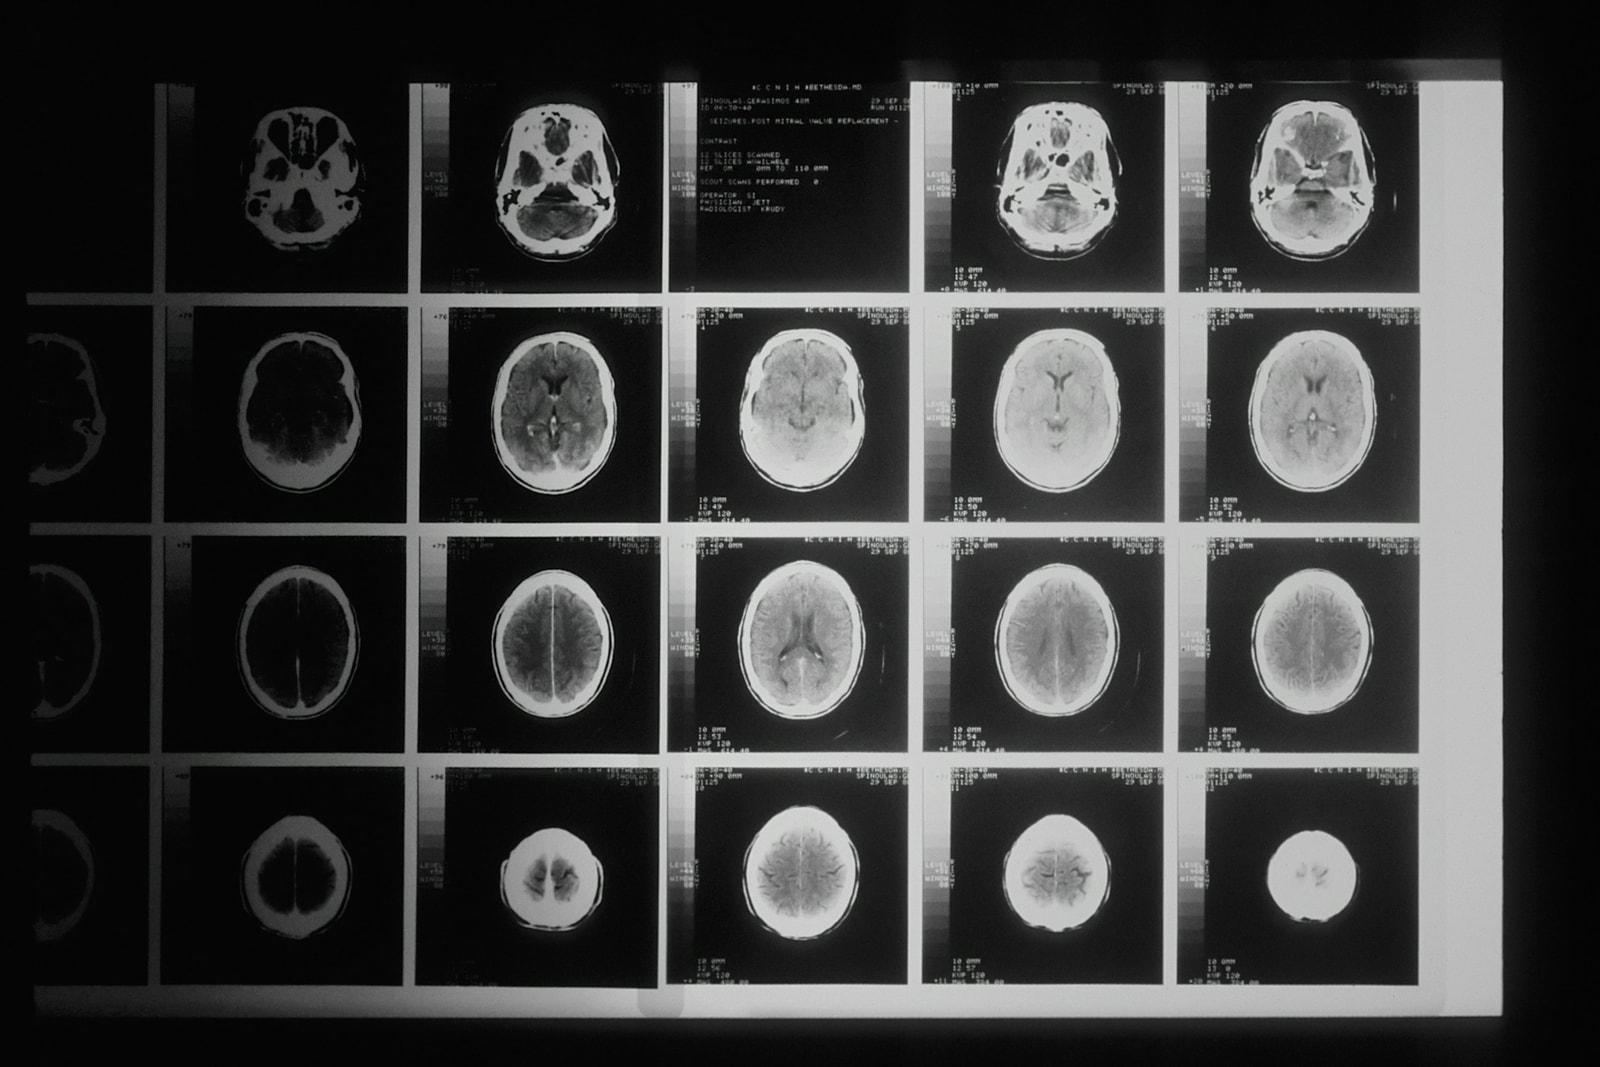

Udar mózgu to jedna z głównych przyczyn niepełnosprawności na świecie. W Polsce każdego roku odnotowuje się ponad 60 tys. przypadków udaru, z czego znaczna część pacjentów zmaga się później z różnymi deficytami neurologicznymi. Apatia poudarowa, choć mniej widoczna niż niedowład czy afazja, może w równym stopniu utrudniać powrót do codziennego funkcjonowania. Niestety, wciąż brakuje dla niej skutecznych metod leczenia. Tym większe znaczenie ma próba stworzenia celowanego, nowoczesnego leku, który przywróci pacjentom nie tylko energię, ale i chęć do życia.